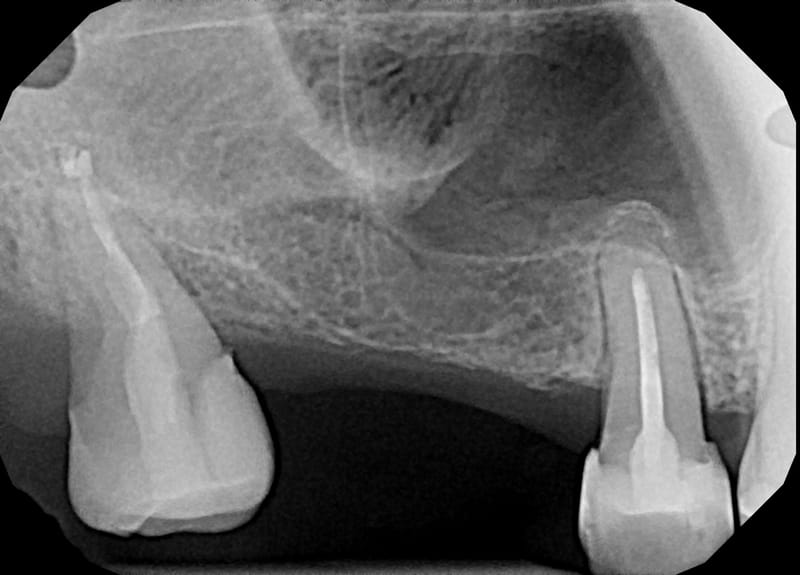

Leczenie pierwotne bezinstrumentacyjne d.18